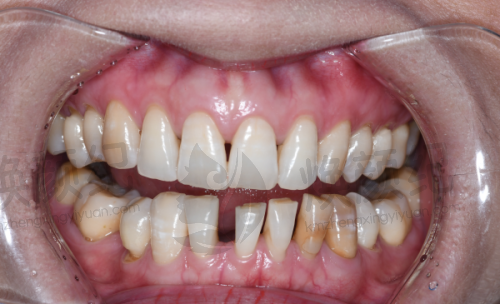

缺牙后选种植牙,特别多人都想参考真实实例,看看不同口腔条件下的治疗成效、修复过程和实际体验。营口团圆口腔肖宏亮医生深耕种植领域17年,接诊过各类缺牙病例,从单颗缺失到半口复杂种植都有丰富经验。下面分享3个不同类型的真实实例,从患者视角还原诊疗过程,给有需求的朋友提供参考,所有实例均经患者同意,无夸张表述。